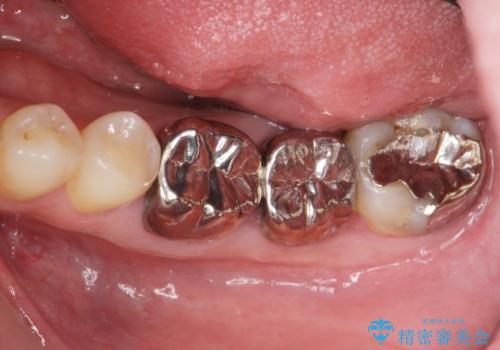

- 銀歯・虫歯・治療途中の歯を治していきたい、セラミックの歯にしたい!と希望され来院されました。

銀歯の下で再発した虫歯や、根尖病変等、多々の問題が認められましたがひとつづつ丁寧に改善し、長期的な予後の見込めるセラミック治療を行っていきます。